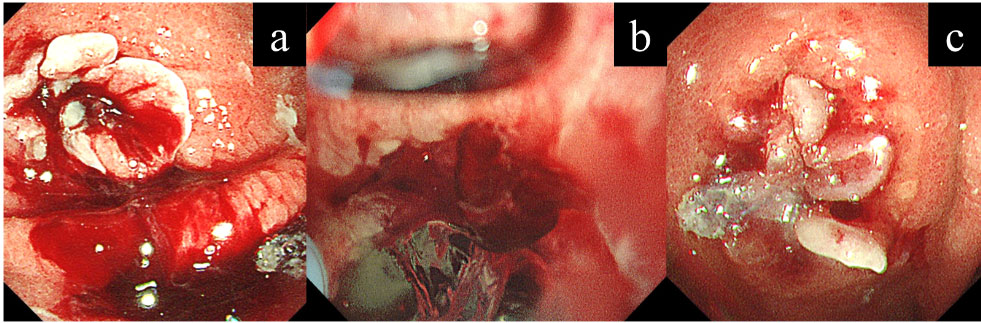

Na sequência ocorreram apresentações de casos clínicos de Paula Peruzzi, Alexandre Iachan e Guilherme Falcão.… SAIBA MAIS